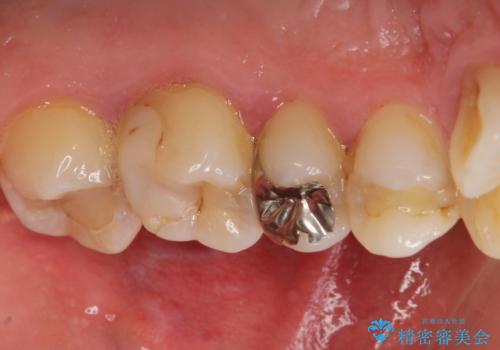

矯正治療とホワイトニングを提案しましたが希望されず、「接客関係の仕事で矯正治療は考えられない、短期間で治療を終わらせたい、ホワイトニングでは難しい位の人工的な白さにしたい」とのご要望により、治療前にワックスアップ模型を作製し何度もコンサルテーションを重ね、治療方針を決定しました。

歯頚ラインが変えられないことや天然歯を削るリスクをご理解頂いた上で、オールセラミッククラウンによる補綴治療を行いました。(見えない奥歯のみ天然歯のままとしました)

下の前歯1本だけ歯軸を変えるために神経をとり根管治療を行っております。

それ以外の歯は神経をとらずに済むよう、慎重かつ丁寧に歯の形態を整えました。